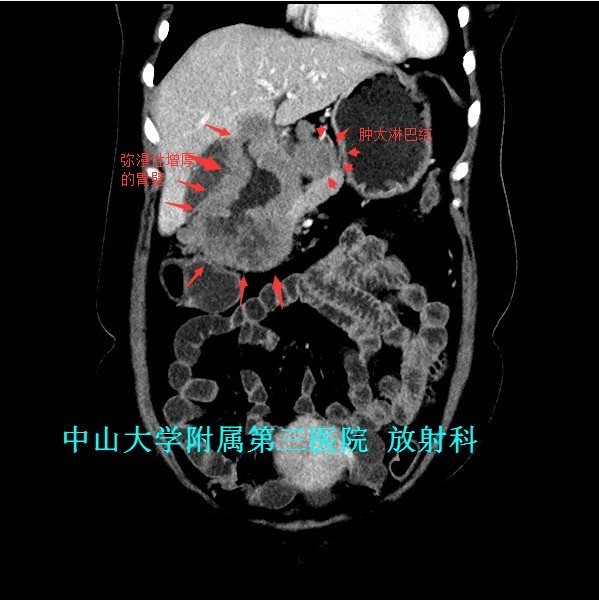

主诉:反复上腹痛1月,黑便1周 病史:46岁女性,急性起病。患者1月前反复出现进食后上腹部疼痛,伴恶心、呕吐。1周前出现黑便,伴头晕、乏力,抑酸、护胃、止血等处理后,症状缓解,门诊拟“上消化道出血”收入我科。

查体:腹软,上腹部轻压痛、无反跳痛,未触及包块。 辅查:1、胃镜:胃十二指肠恶性病变(待病理);2、上腹部CT:胃窦至十二指肠胃壁弥漫性增厚,考虑淋巴瘤可能性大。

诊断:胃淋巴瘤 治疗:入院排除手术禁忌证后,于全麻下行“剖腹探查术”,术中发现胃肿物无法切除并幽门梗阻,遂决定行“胃肿物活检术+胃空肠吻合术”,术后病理提示“B细胞源性非霍奇金性淋巴瘤”,免疫组化示“CK(-),CEA(-),Vim(部分+),CD3(部分+),CD45RO(部分+),CD20(+),CD79α(+),CD56(-),TIA1(散在+),CK20(-),Ki-67(40%+),P53(+)。”。建议转血液科进行下一步内科治疗,患者拒绝转科并签字出院。

讨论:原发性胃肠道淋巴瘤是一组起源于胃肠道黏膜下层淋巴组织的恶性肿瘤,成人较少见,约占胃肠道恶性肿瘤的1~4% 。影像表现具有一定特征性:弥漫性或局限性胃壁增厚是胃淋巴瘤主要特征,增厚的胃壁内缘呈波浪样或分叶状,外缘较光整,胃腔有一定的扩张度,增强扫描动脉期呈轻中度强化,静脉期持续强化。主要与胃癌鉴别,胃癌也表现为胃壁增厚,但一般增厚无淋巴瘤明显,而且胃壁僵硬,官腔变窄,常有浸润周围组织器官。 参考文献:侯明杰,齐鹏飞,高万勤等.原发胃肠道淋巴瘤的影像表现和误诊分析[J].实用放射学杂志,2014,(12):2112-2113,2121.